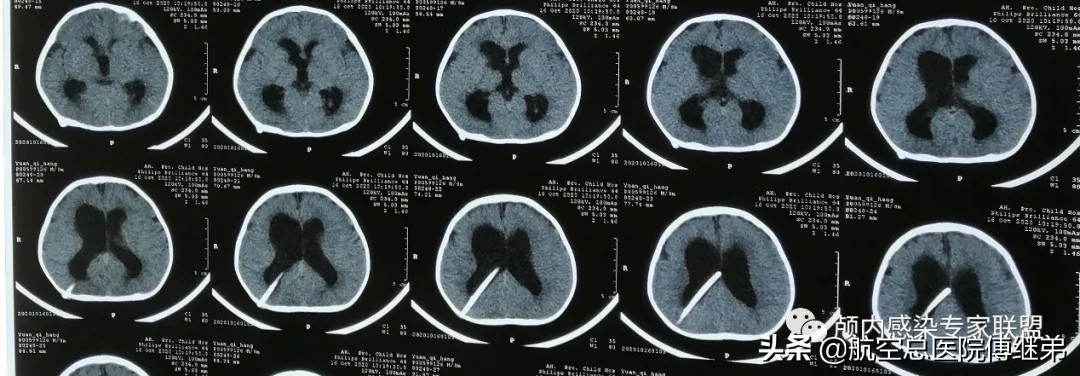

在患儿约10个月大即2020年09月份时家属发现患儿发育较同龄人缓慢,没有言语,不会爬也不能走,为了治疗就诊于浙江大学附属儿童医院,医院诊断为脑积水,并于当时给予行 第一次 脑室腹腔分流术,术后复查颅脑CT可见分流管位置可。(图二)

图二:第一次脑室腹腔分流术后